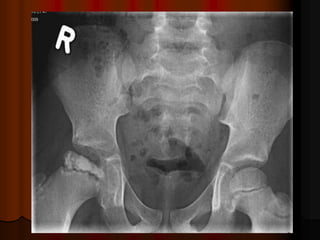

Ankylosing spondylitis

It is an inflammatory disease and one of the sero –ve

spondyloarthropathies.

It is primarily a disease of the spine and sacroiliac joint.

It affects the proximal joints especially the hips.

One or both hips may be affected with pain and stiffness which

improve by exercises.

Hip involvement may be so severe--------- hip replacement is

indicated.